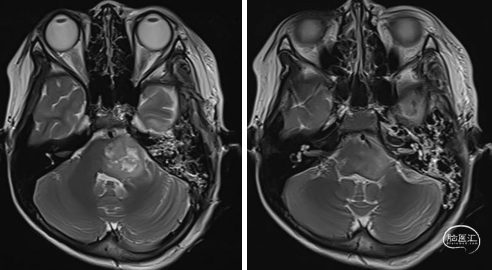

2023年9月13日 MRI T2

2023年9月13日 MRI+C